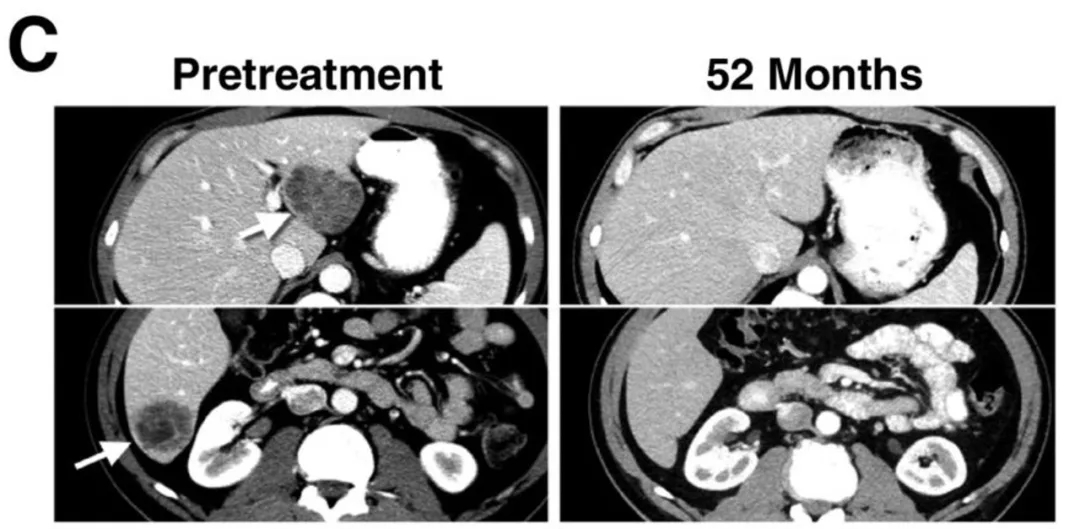

在黑色素瘤患者中,11例缓解患者均在首次接受1G4-αLYTCR转导T细胞治疗后,出现客观缓解。其中4例患者达到完全缓解(CR),3例在治疗后40~58个月仍维持完全缓解。另有7例患者达到部分缓解(PR),持续时间为3~28个月;37号患者在输注后6个月仍维持部分缓解,因出现无关第二种癌症终止随访。该组患者3年和5年总生存率估计值均为33%(详见下图B)。

值得关注的是,CT及放射学检查清晰记录了典型患者的肿瘤消退情况:29号患者的肝脏和肺部多发转移灶完全消退(详见下图C/D),疗效维持54个月以上。